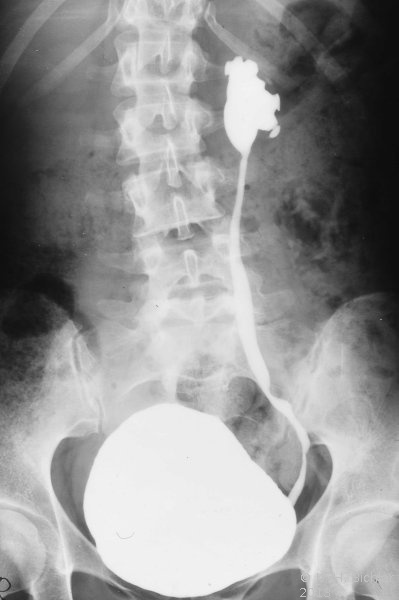

Neben der Anamnese, körperlicher Untersuchung, Messung des Blutdruckes sowie der Laboruntersuchungen: Urinstatus, Serumkreatinin und -Elektroylte ist die Sonographie zur Feststellung einer einseitig kleinen Niere zielführend (Abbildung 10a). Zur Diagnostik zählt fernerhin die NFZG (Abbildung 10b) bzw. Computertomographie.

Die Abbildungen zeigen die Anwendung von Sonographie und Miktionszysturethrogramm bei einer kleinen stummen Niere (Abbildung 13, 14).